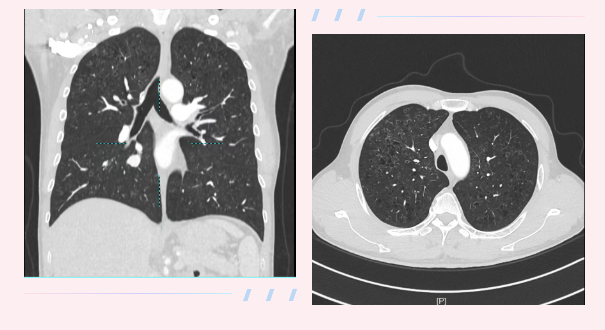

肺部CT结果让人警惕——双肺多发囊性病变,形态不规则,分布不均,呈“蜂窝样”改变。这种影像表现,并不典型属于普通慢阻肺。